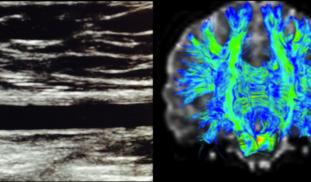

Our group has been intensely studying how vascular and cognitive health intersect. The clustering of cardiovascular risk factors and insulin insensitivity, known as metabolic syndrome, in a single individual is a growing public health concern. We are trying to understand the impact of metabolic syndrome components on vascular health, brain structure and cognitive function.